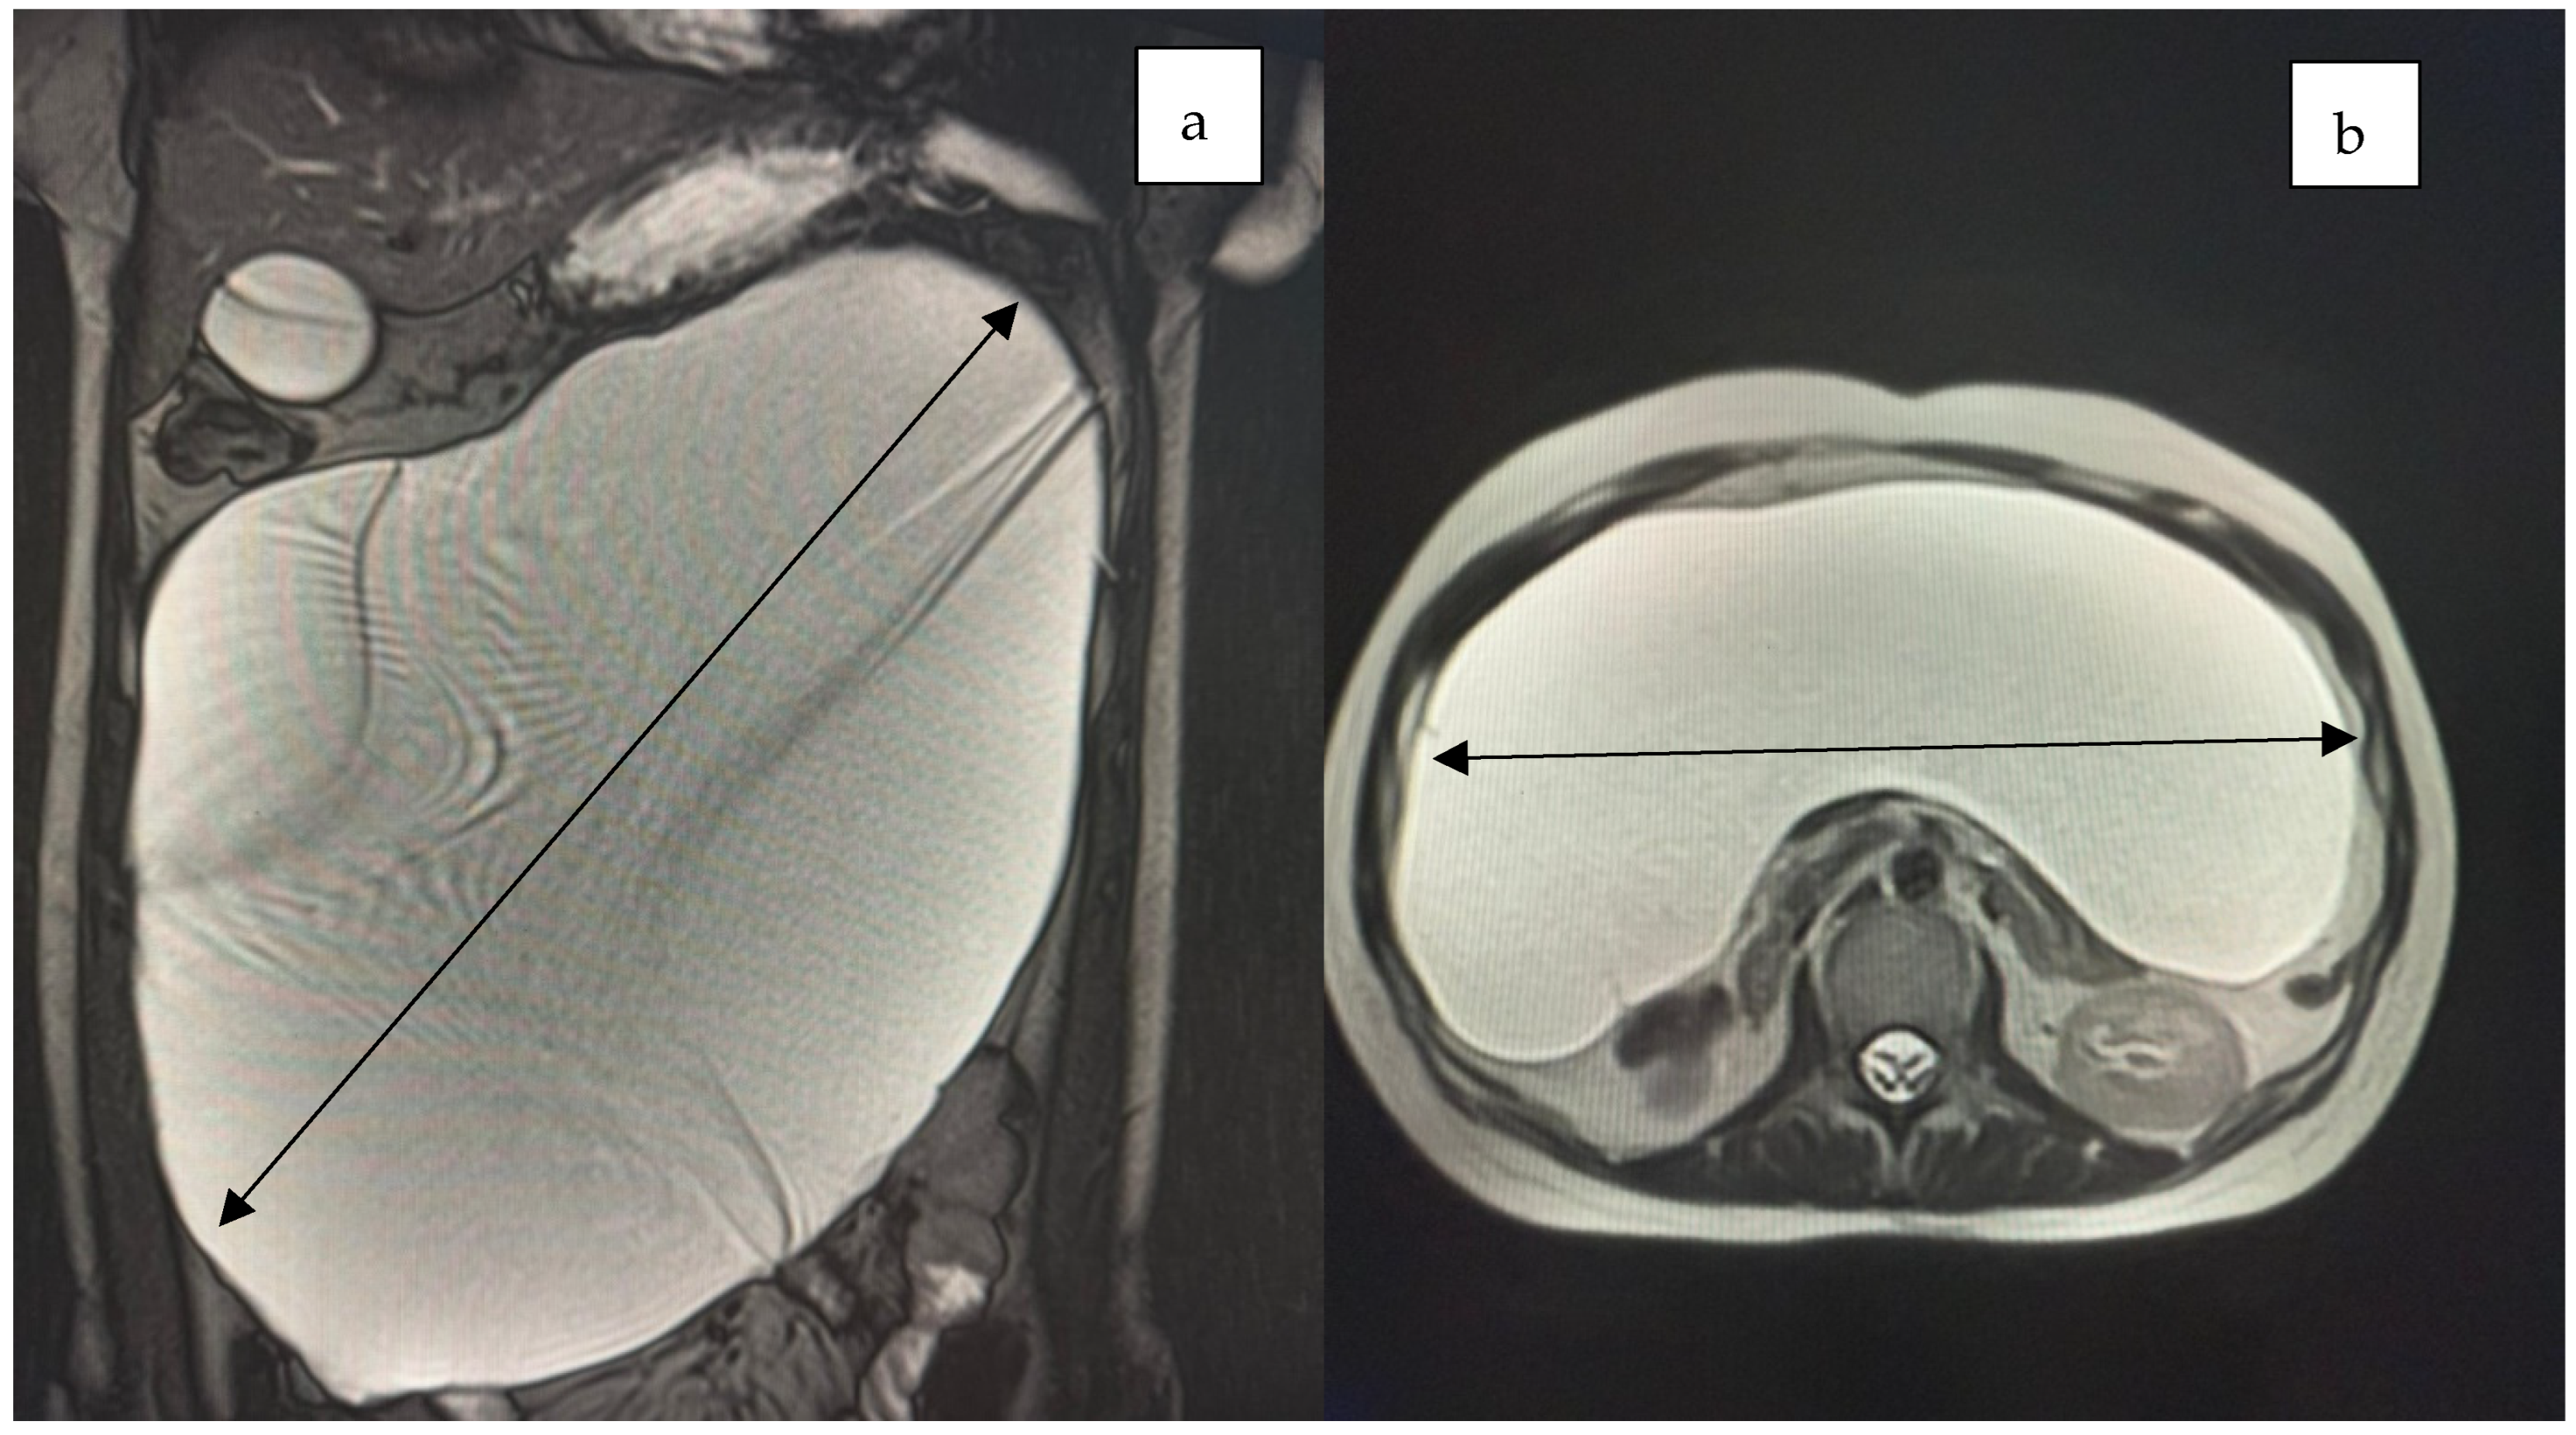

2. Case Presentation